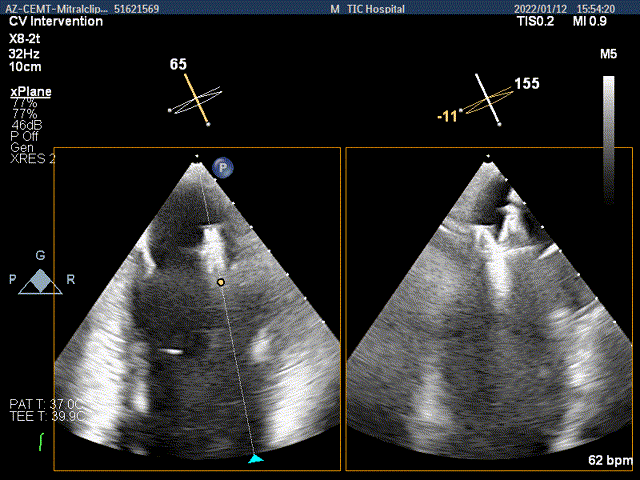

x-plane验证前后叶抓捕后bond明显

x-plane验证前后叶抓捕后跳跃征明显